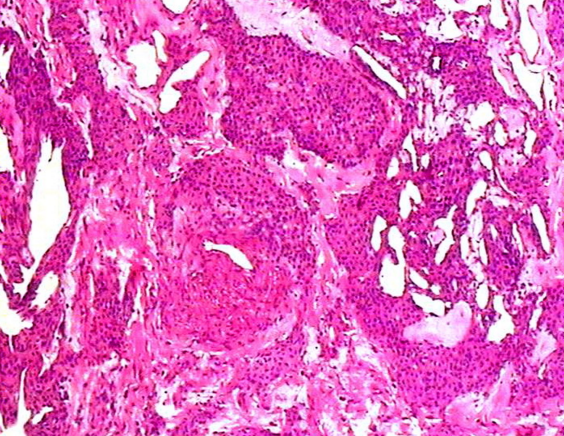

什么是血管球瘤?

血管球瘤病理及鉴别诊断